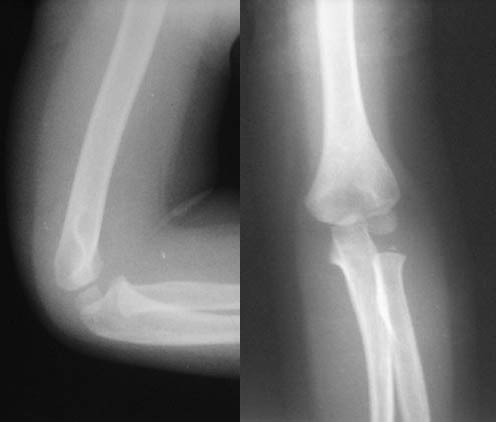

男儿,5岁,左肘部外伤,局部肿胀一天。

左肱骨小头上方骨皮质不连续,隐示一';线';型骨折线,软组织肿胀,考虑左肱骨小头骨骺分离

左肱骨小头[肱骨小头位于前线之前,9岁以下应该位于前线之后]上方骨皮质不连续,隐示一';线';型骨折线,软组织肿胀,考虑左肱骨小头骨骺分离。

左肱骨小头骨骺干骺端骨折。

[quote]以下是引用wk8888在2006-5-22 19:48:00的发言:[br]左肱骨小头上方骨皮质不连续,隐示一';线';型骨折线,软组织肿胀,考虑左肱骨小头干骺端青枝骨折

表现:正位肱骨远侧干骺端可见横行低密度线延伸至外髁,外髁皮质断裂,侧位前侧骨皮质也有断裂。对侧好像有类似之处,但那是与肱骨小头骨骺的重叠影。

印象:肱骨低位髁上骨折